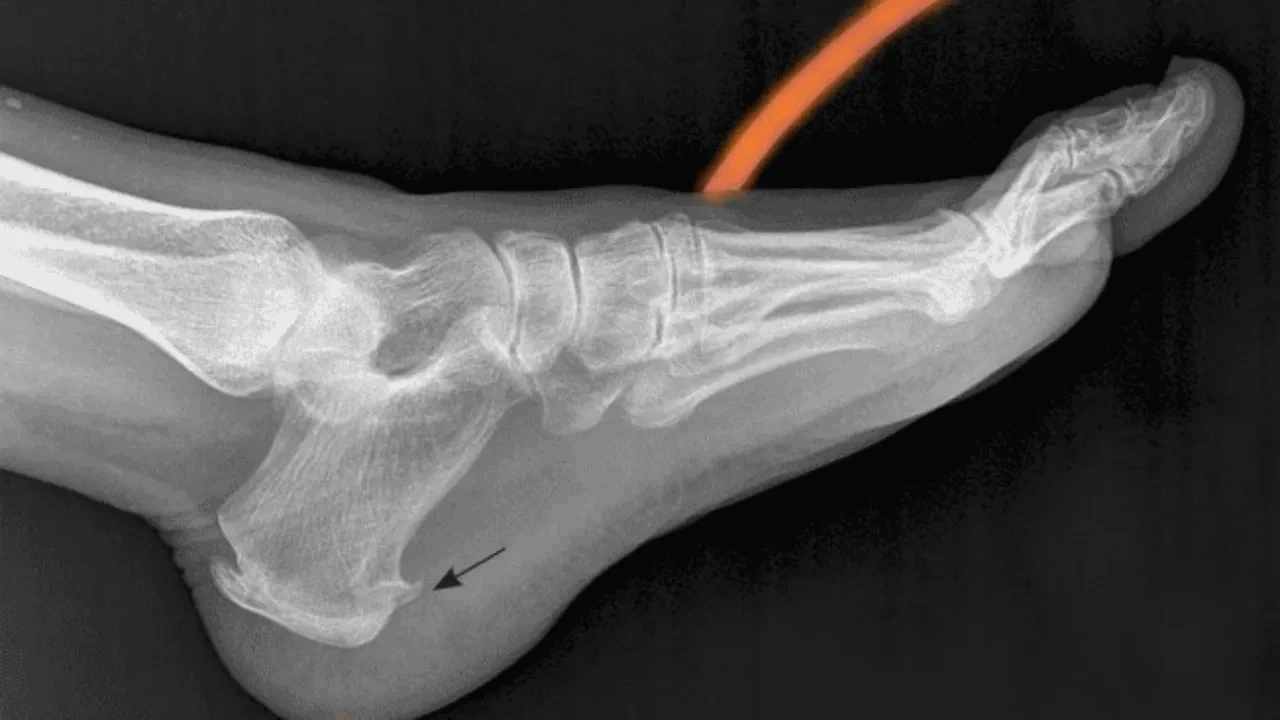

"Ayak tabanındaki bağ dokusunun topuk kemiğine yapıştığı noktada kalsiyum birikmesiyle oluşan kemiksi bir çıkıntıdır. En belirgin belirtisi ise sabahları ilk adımda hissedilen keskin, bıçak saplanır gibi bir ağrıdır."

Bu ağrının altında genellikle plantar fasiit adı verilen bağ dokusu iltihabı yatıyor.